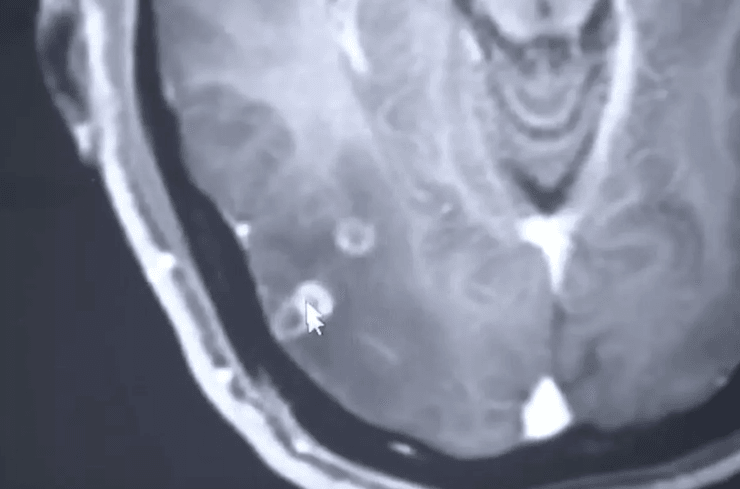

"В мозге пациента имеются множественные очаги пространственно-занимающих поражений. Они также находятся в легких и заполняют мышцы в грудной полости", — говорится в сообщении.

Когда терпеть уже было невозможно он обратился к врачу. Пациент заметил, что судороги и мигрень у него начинались после того, как он употреблял в пищу свинину. В результате по всему телу, включая мозг, у него обнаружили ленточные черви, а в больнице диагностировали кишечную паразитарную инфекцию тениоз.